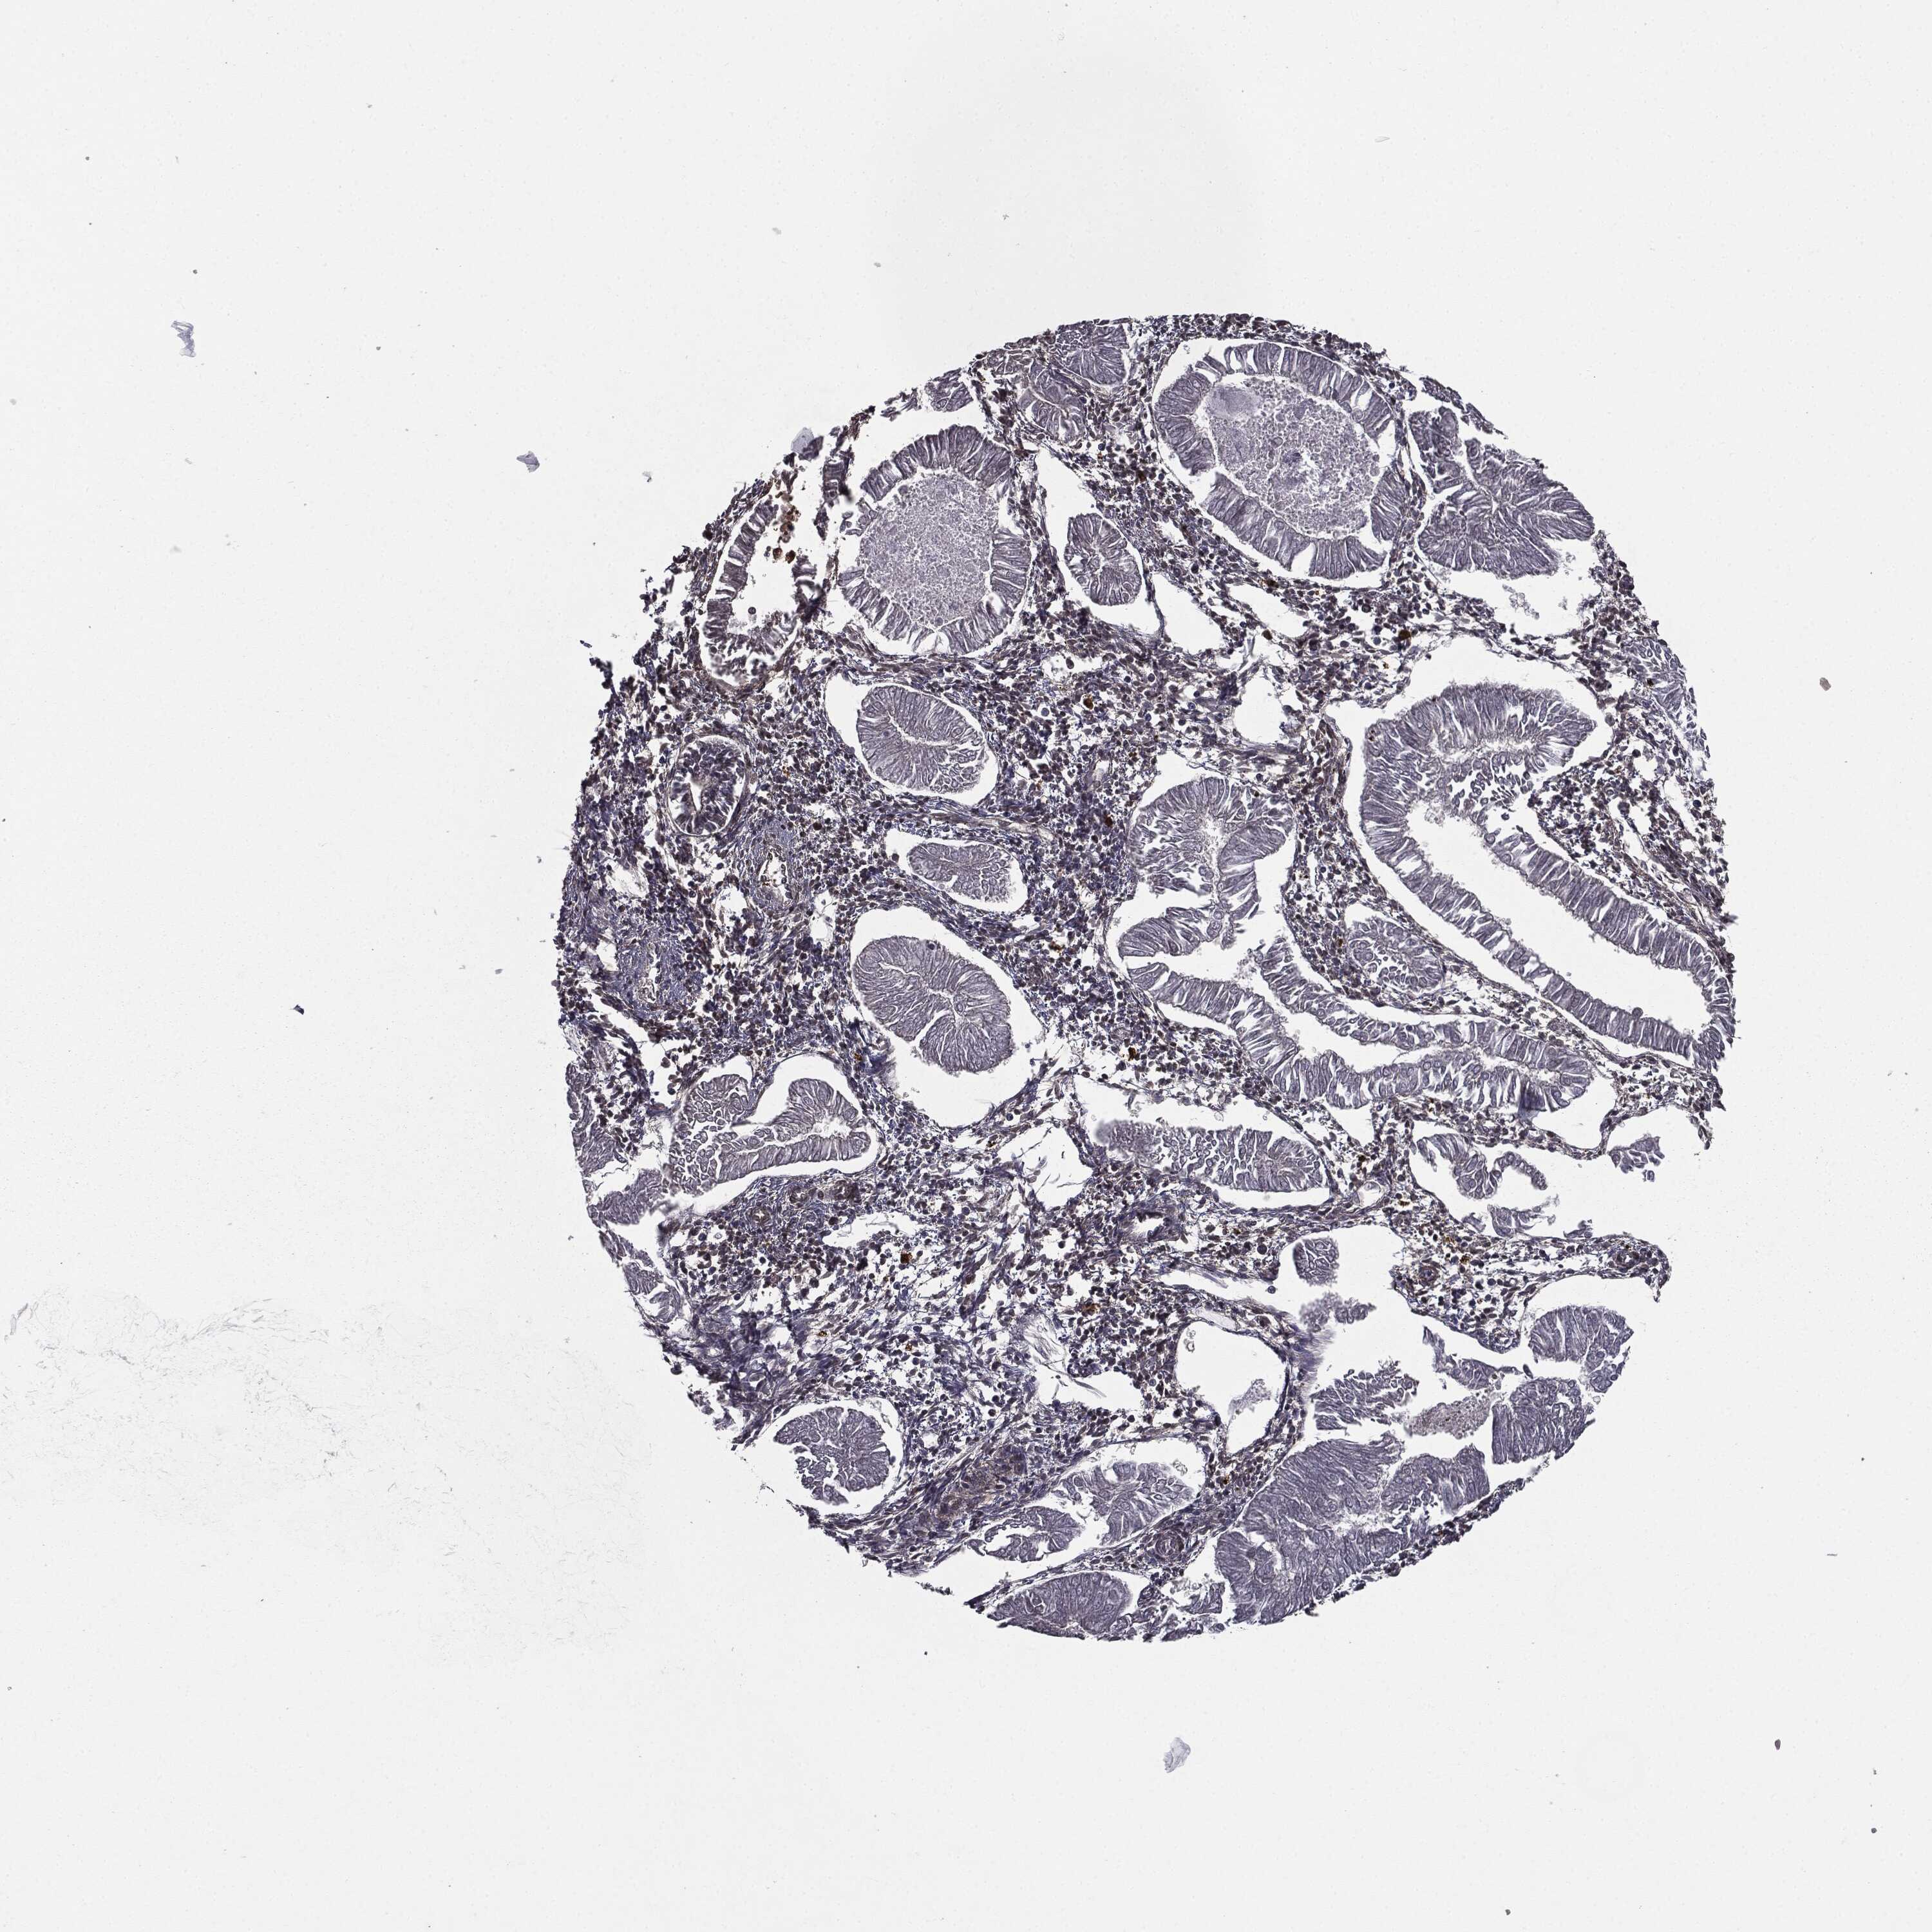

ENDOMETRIAL CANCER - Protein expressioni

A mouse-over function shows sample information and annotation data. Click on an image to view it in a full screen mode. Samples can be filtered based on level of antibody staining by selecting one or several of the following categories: high, medium, low and not detected. The assay and annotation is described here.

Note that samples used for immunohistochemistry by the Human Protein Atlas do not correspond to samples in the TCGA dataset.

Antibody stainingi

Antibody staining in the annotated cell types in the current human tissue is reported as not detected, low, medium, or high, based on conventional immunohistochemistry profiling in selected tissues. This score is based on the combination of the staining intensity and fraction of stained cells.

Each image is clickable and will lead to virtual microscopy that enables deeper exploration of all samples and also displays staining intensity scores, fraction scores and subcellular localization as well as patient and tissue information for each sample.

Antibody HPA052606

Antibody HPA077139

Staining

High

Medium

Low

Not detected

Intensity

Strong

Moderate

Weak

Negative

Quantity

>75%

75%-25%

<25%

None

Location

Nuclear

Cytoplasmic/membranous

Cytoplasmic/membranous,nuclear

Adenocarcinoma, NOS